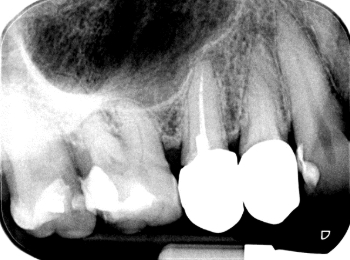

Röntgen Revision 25

Zustand nach Revision 25 und Extraktion 26 und 27.